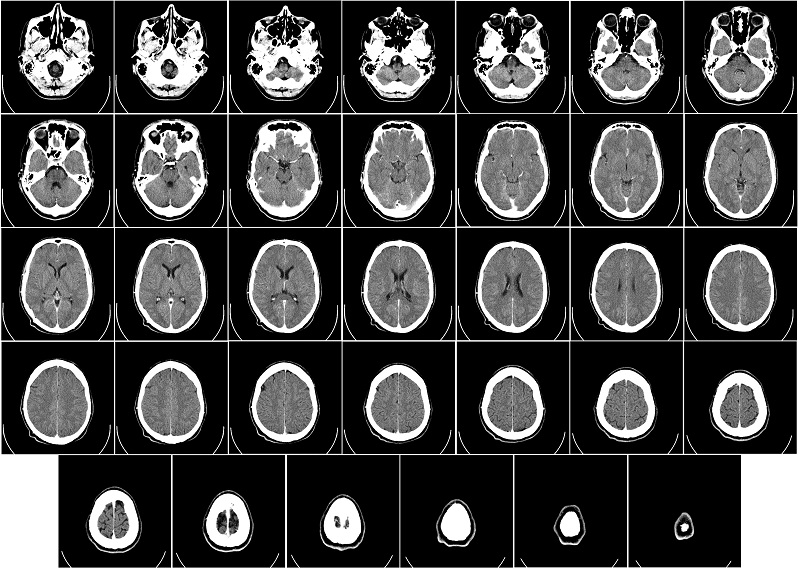

CT scan là từ viết tắt của Computed Tomography Scan, tức là chụp cắt lớp vi tính. Khi thực hiện chụp CT, chùm tia X được phóng vào cơ thể theo lát cắt ngang. Thông qua máy tính xử lý cho ra hình ảnh 2 chiều, 3 chiều rõ nét. Độ sắc nét của hình ảnh phụ thuộc vào độ phân giải của thế hệ máy chụp gồm 64 lát cắt, 16 lát cắt, 4 lát cắt,... Số lát cắt tỉ lệ thuận với độ nét của hình ảnh.

Tương tự như vậy, khi tiến hành chụp CT não, một chùm tia X được phóng theo lát cắt ngang vào khu vực não bộ của người bệnh. Hình ảnh bên trong được tái hiện rõ nét. Đồng thời nếu có tổn thương về não sẽ được hiển thị bằng tăng độ đậm hoặc giảm độ đậm trên những khu vực bị tổn thương đó.